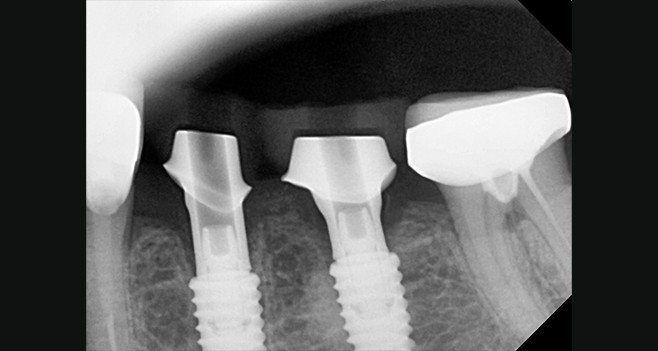

커스텀 안착상태 페리사진

보철셋팅